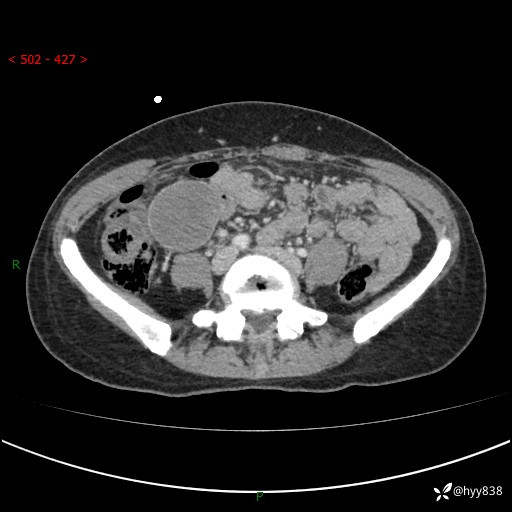

年轻女性,发现腹腔肿物1周。圆圆的肿物,诊断有难度---结果公布~

主诉:发现腹腔肿物1周

现病史:患者自诉于1周前无明显诱因出现剑突下间断性隐痛,尚可忍受,不向其它部位放射,无恶心呕吐、腹泻便秘等不适,于当地市第二人民医院就诊,行CT结果示:1.右中腹占位,间叶组织来源可能2.小肠梗阻3.盆腔积液4.腹腔积液5.副脾6.肝囊肿;于荆州二医行抗炎,抑酸,护胃,补液等对症支持治疗;患者病情好转,今为求进一步诊治,遂来我院门诊就诊,门诊以“腹腔肿瘤”收入院。 起病以来,患者精神、睡眠、饮食一般,大小便正常,近期体力体重无明显改变。

腹部CT增强(外院平扫)